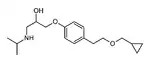

Propanolamines are a class of chemical compounds, many of which are pharmaceutical drugs. They are amino alcohols that are derivatives of 1-amino-2-propanol.[1]

Propanolamines include: